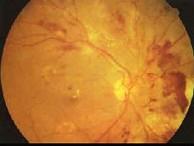

糖尿病眼部病变中导致失明的主要原因是()A.白内障B.微血管瘤C.硬性渗出D.视网膜小静脉扩张E.增殖性视网膜病变

问题 糖尿病眼部病变中导致失明的主要原因是()

选项 A.白内障 B.微血管瘤 C.硬性渗出 D.视网膜小静脉扩张 E.增殖性视网膜病变

答案 E